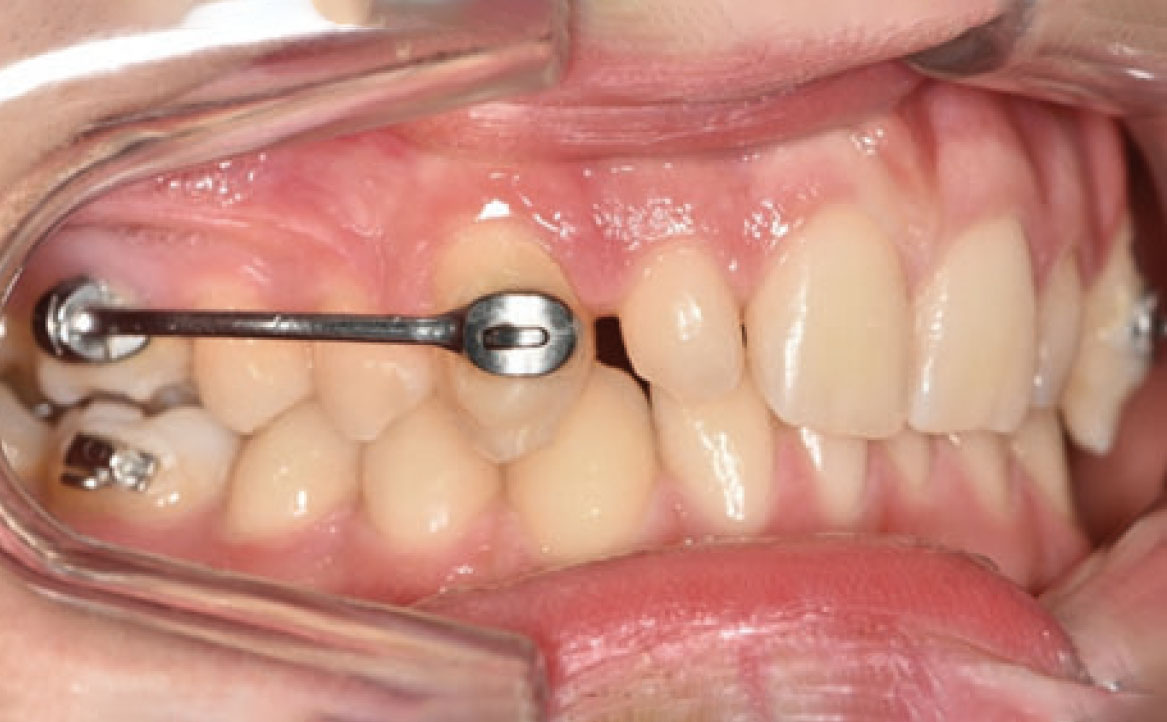

In primo luogo, sono stati prescritti entrambi gli esami radiografici ortodontici: OPT e teleradiografia latero-laterale del cranio (fig. 2a-b). Successivamente, in accordo con il genitore, è stata concordata una terapia ortodontica in due tempi. L’inizio della terapia è stato effettuato con Carriere Motion ed elastici di classe II, con l’obiettivo di migliorare la classe molare (fig. 2c-e).

Infatti, durante il primo controllo due mesi dopo, è stato osservato un miglioramento della classe molare (fig. 3a-c).